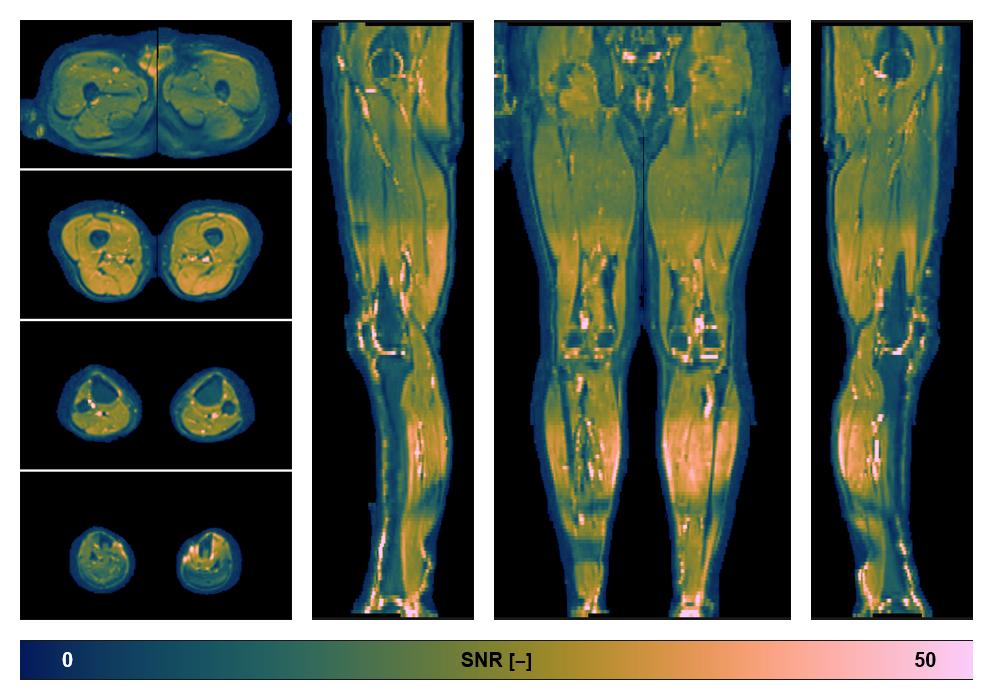

• SNR distribution

The SNR distribution of the dixon data.

• SNR of the unweighted image

SNR distribution of the unweighted diffusion data.